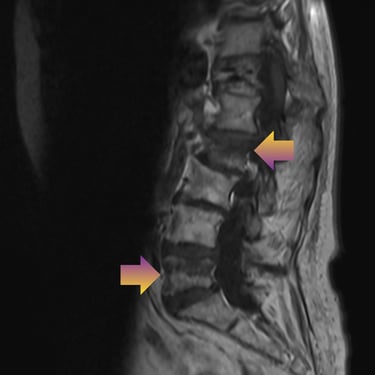

🧠Compresión medular cervical y dorsal: tratamiento mediante artrodesis y descompresión nerviosa.

La compresión medular cervical y dorsal es una patología grave que puede ocasionar déficit neurológico progresivo. La descompresión quirúrgica asociada a artrodesis vertebral permite liberar la médula espinal y estabilizar la columna, mejorando la función neurológica y evitando el deterioro clínico en pacientes adecuadamente seleccionados.